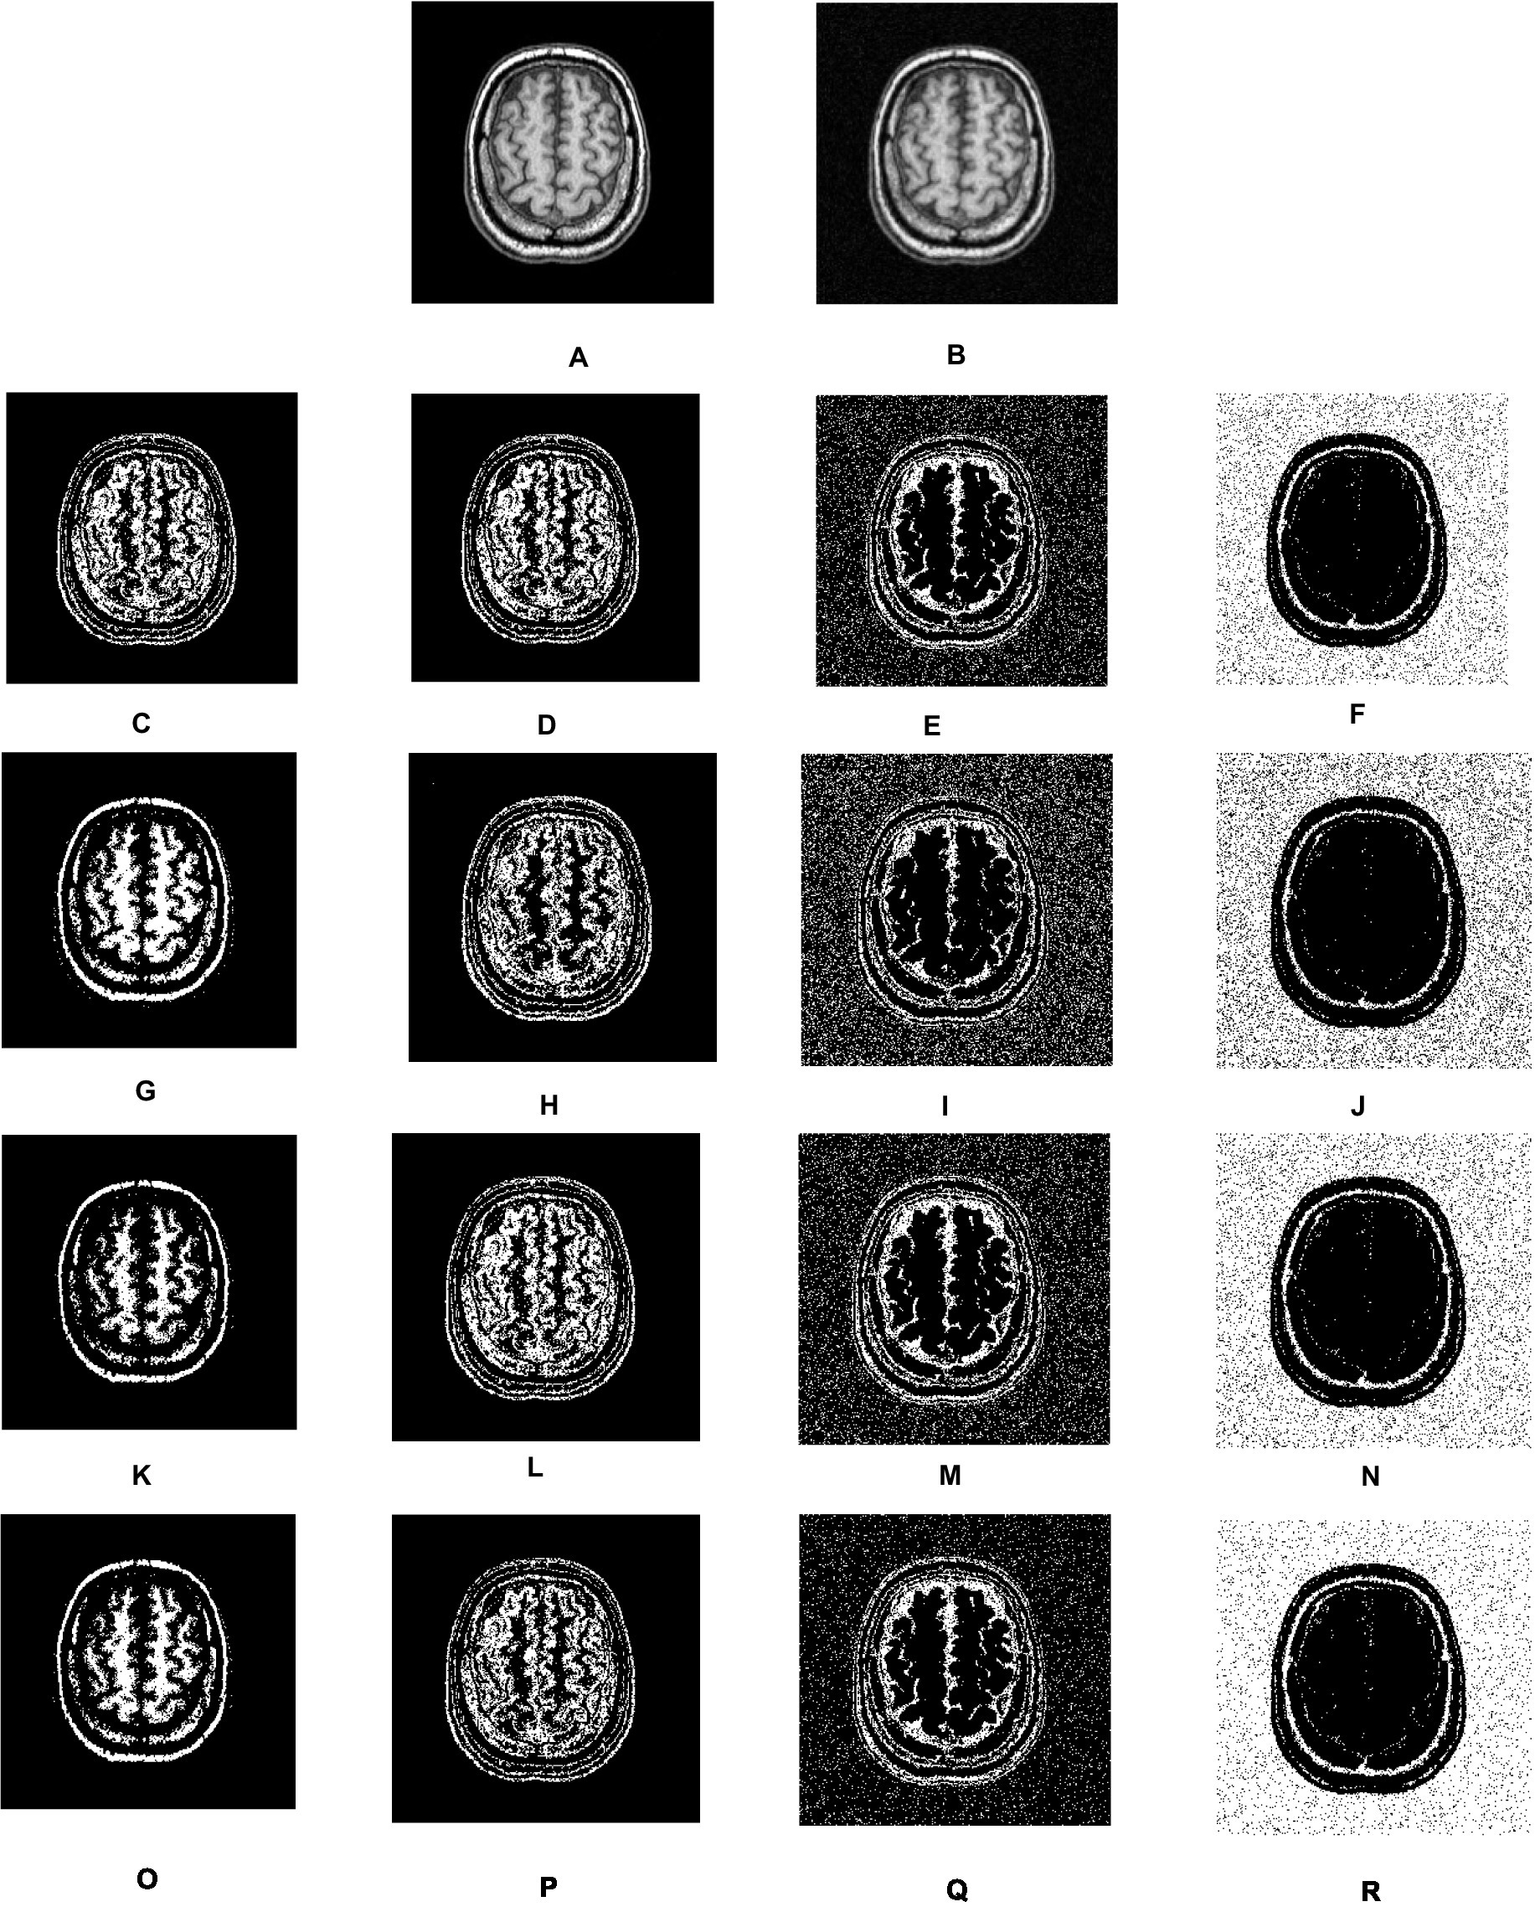

Figure 4

Visual results of segmentation on synthetic image of phantom. (A) Phantom image. (B) Noisy images. (C–F) Results of FCM. (G–J) Results of IFCM. (K–N) Results of csFCM. (O–R) Results of csIFCM.

To show the effectiveness of the algorithm against noise, we have embedded an image with 0.01% of Gaussian noise. Figures 4A,B depict the original and noisy images, respectively. The noisy image’s segmented sections, produced by the FCM algorithm, are displayed in Figures 4C–F. Figures 4G–J displays the IFCM result. The results of csFCM are displayed in Figures 4K–N, and the suggested csIFCM algorithm produces results with more qualitative accuracy and greater noise resilience in Figures 4O–R.